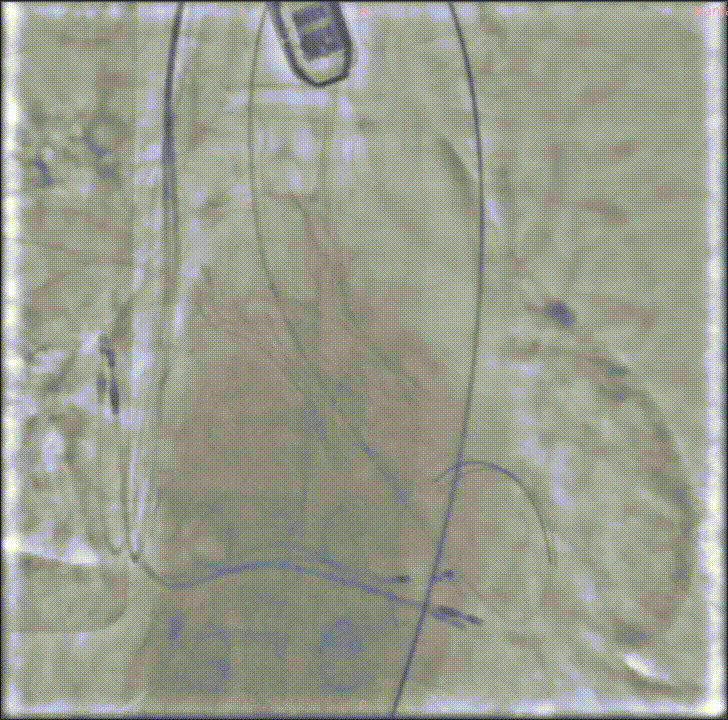

经过充分的术前评估和准备,修建成教授带领由医院心内、超声、麻醉、放射等多学科成员组成的手术团队,开始了这台TAVR手术。

穿刺、置管、跨瓣、扩张、释放瓣膜、测压、检测、拔管、手术结束……当天的DSA手术台上,修建成教授和团队有条不紊地完成着每一个步骤。术中的每一个步骤、每一个节点、每一个动作,团队每位成员都十分娴熟。最终成功在预定位置精准植入瓣膜。

深度评估

释放后造影

后扩

瓣膜植入后立即进入工作状态,术后造影显示瓣膜工作状态良好,无瓣周漏及明显跨瓣压差;冠脉无阻挡,无传导阻滞

采访中,修建成教授欣慰地分享了手术效果:“手术之后的结果也验证了我们术前的分析和想法。从影像学结果分析来看,我们把瓣周漏减少到非常低的水平,同时瓣膜的扩张、展开都非常好,可以说达到一个非常理想的结果。”